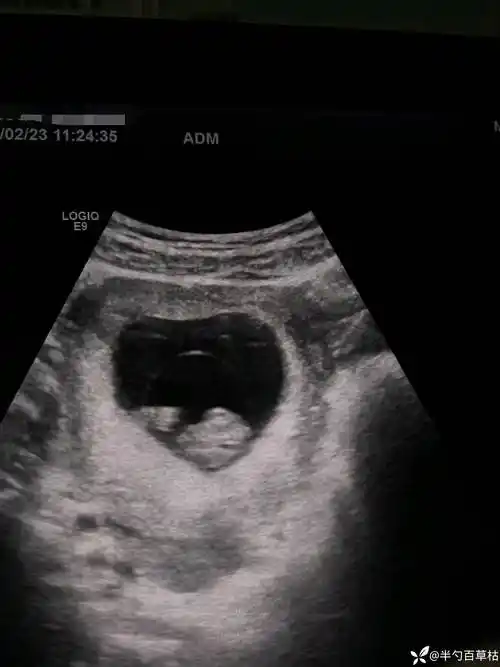

早孕:这个是羊膜囊吗? - 超声医学讨论版 - 爱爱医医学论坛

超声诊断羊膜片1例——zengerya

超声诊断羊膜片1例zengerya